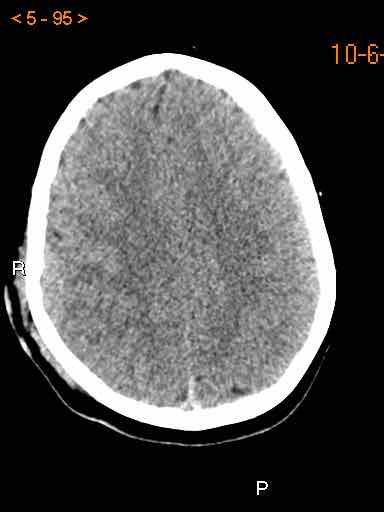

Tụ máu dưới màng cứng đồng tỷ trọng

Khi tụ máu dưới màng cứng tiến triển theo thời gian, tỷ trọng của khối tụ máu sẽ giảm dần và có thể tương đương với tỷ trọng của nhu mô não, khiến việc phát hiện tổn thương trở nên khó khăn.

Đây là trường hợp tụ máu dưới màng cứng đồng tỷ trọng rất khó phát hiện (các mũi tên).

Lưu ý rằng ở mức cắt cao hơn có tụ máu dưới màng cứng hai bên.